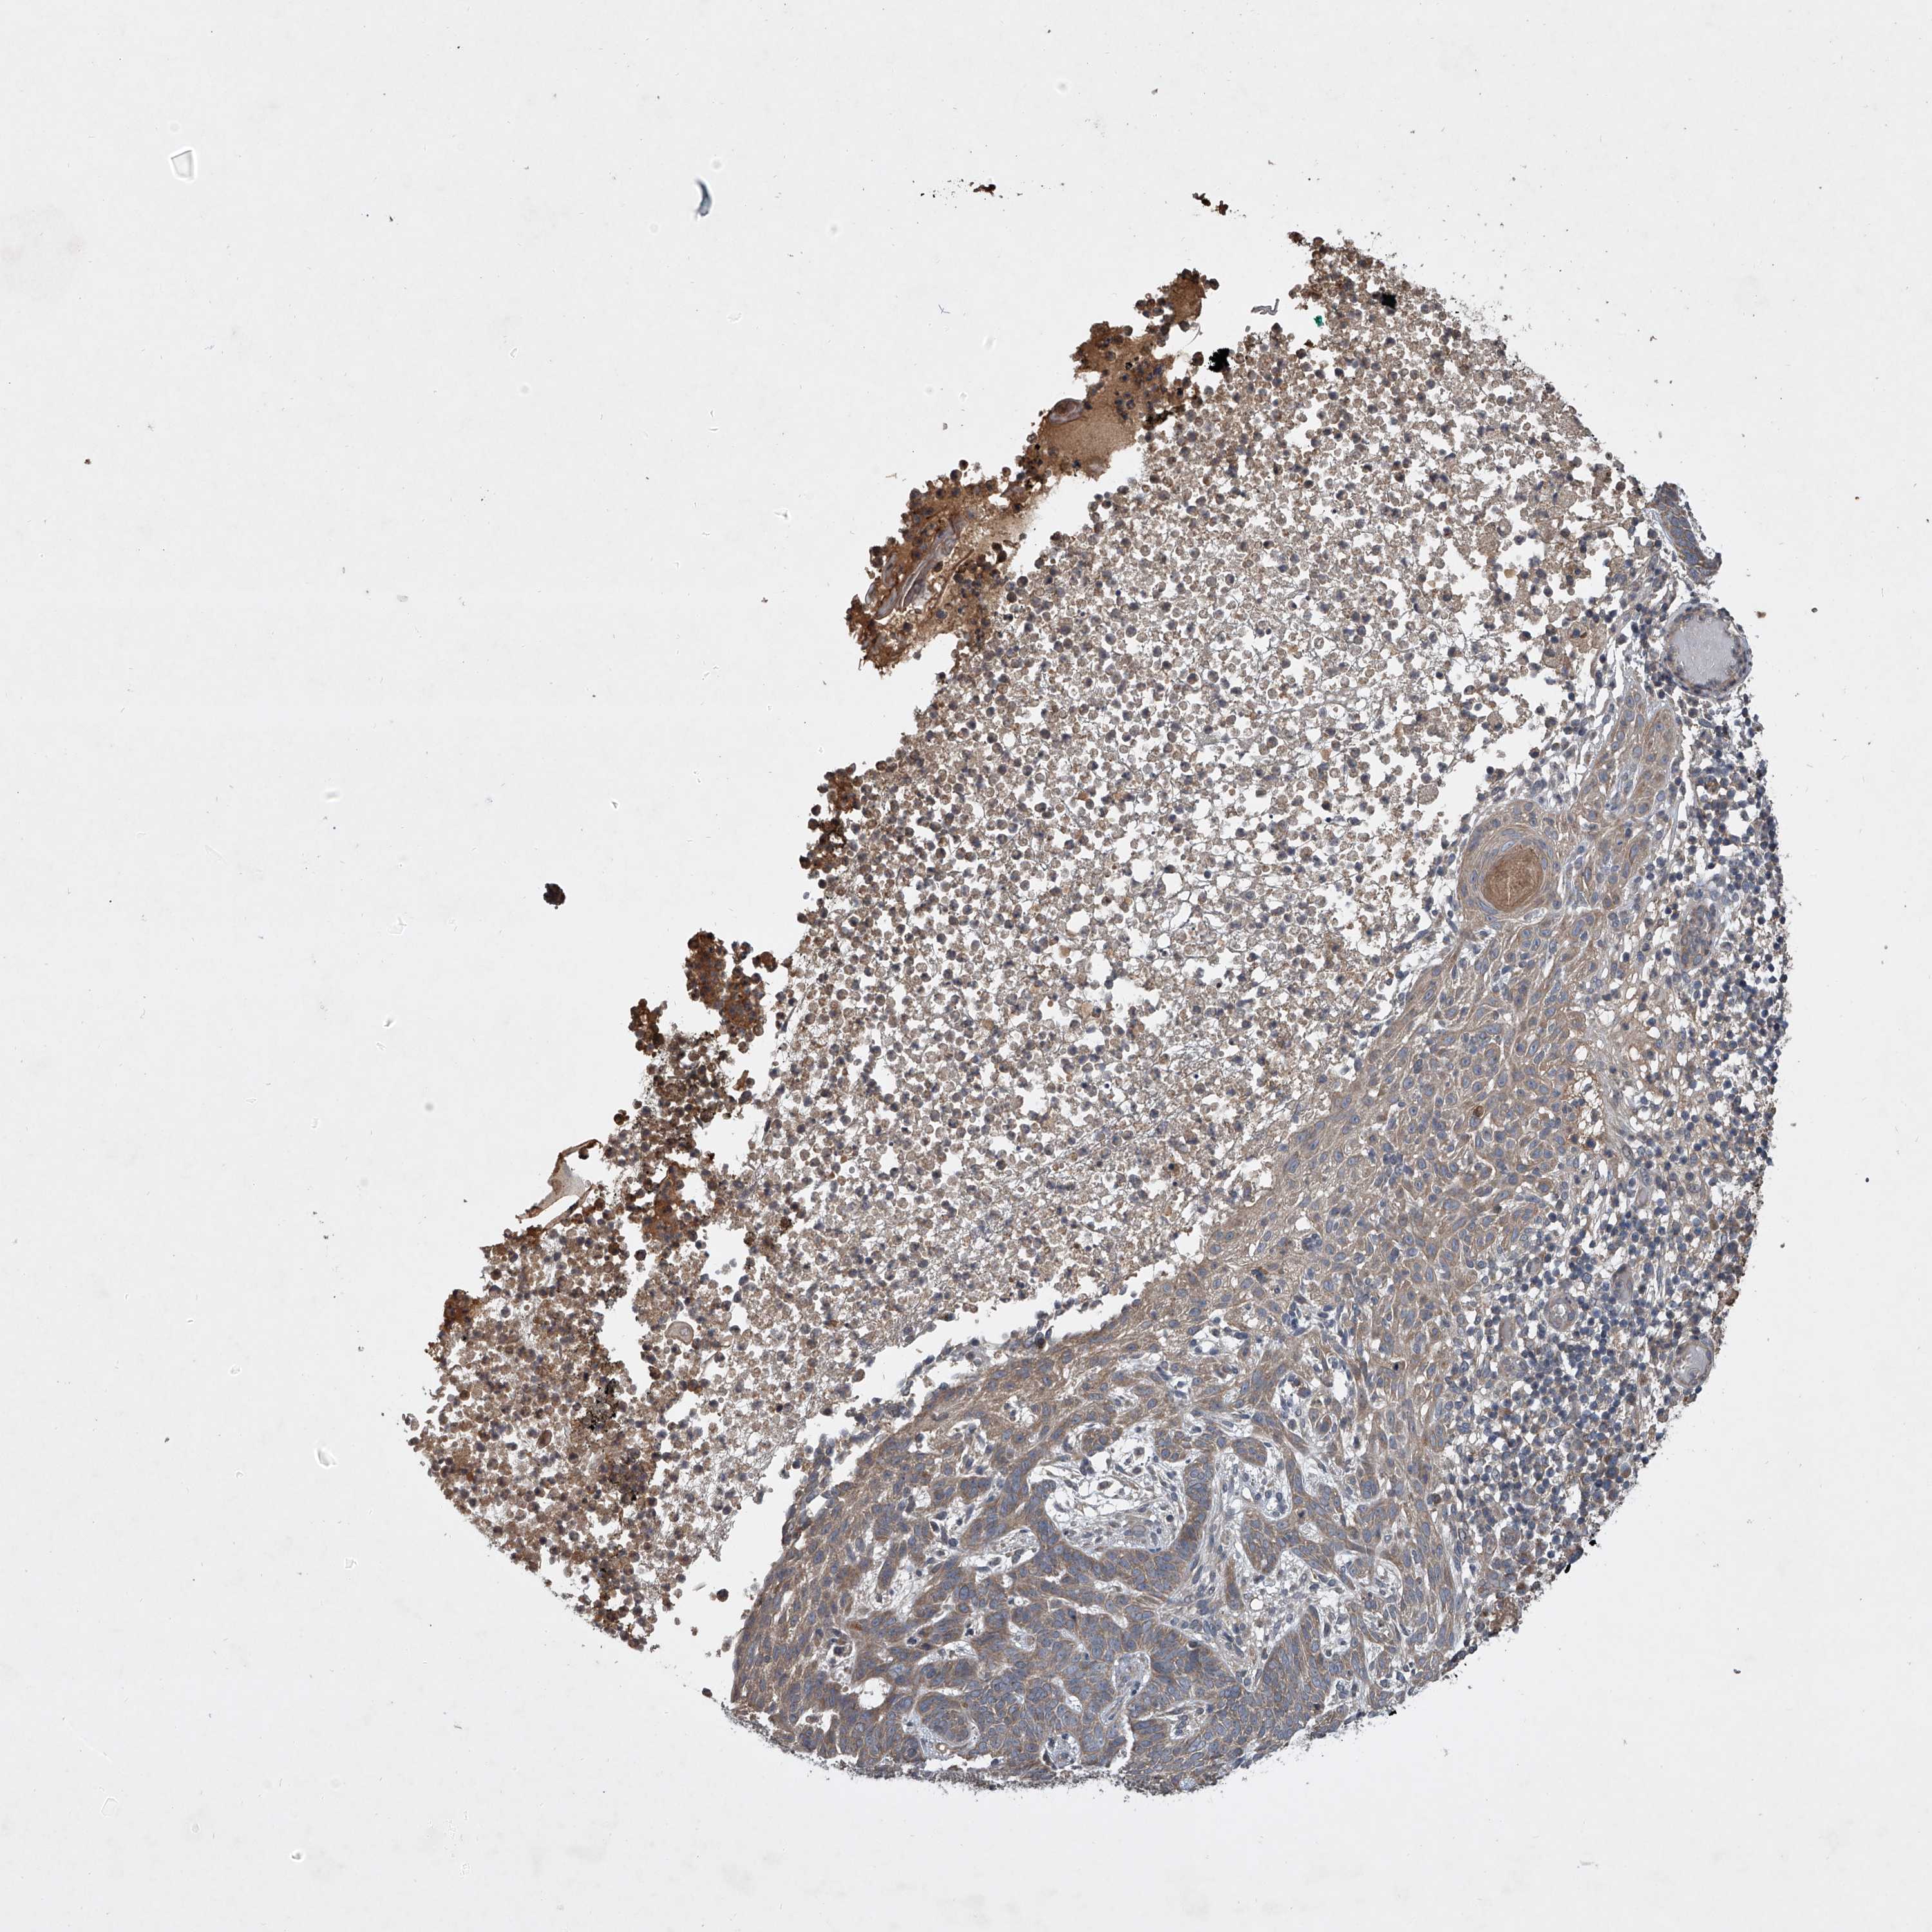

SKIN CANCER - Protein expressioni

A mouse-over function shows sample information and annotation data. Click on an image to view it in a full screen mode. Samples can be filtered based on level of antibody staining by selecting one or several of the following categories: high, medium, low and not detected. The assay and annotation is described here.

Antibody staining in the annotated cell types in the current human tissue is reported as not detected, low, medium, or high, based on conventional immunohistochemistry profiling in selected tissues. This score is based on the combination of the staining intensity and fraction of stained cells.

Each image is clickable and will lead to virtual microscopy that enables deeper exploration of all samples and also displays staining intensity scores, fraction scores and subcellular localization as well as patient and tissue information for each sample.

Antibody HPA051801

Antibody HPA054755

Antibody CAB034314

Basal cell carcinoma

Squamous cell carcinoma, NOS

Squamous cell carcinoma, metastatic, NOS